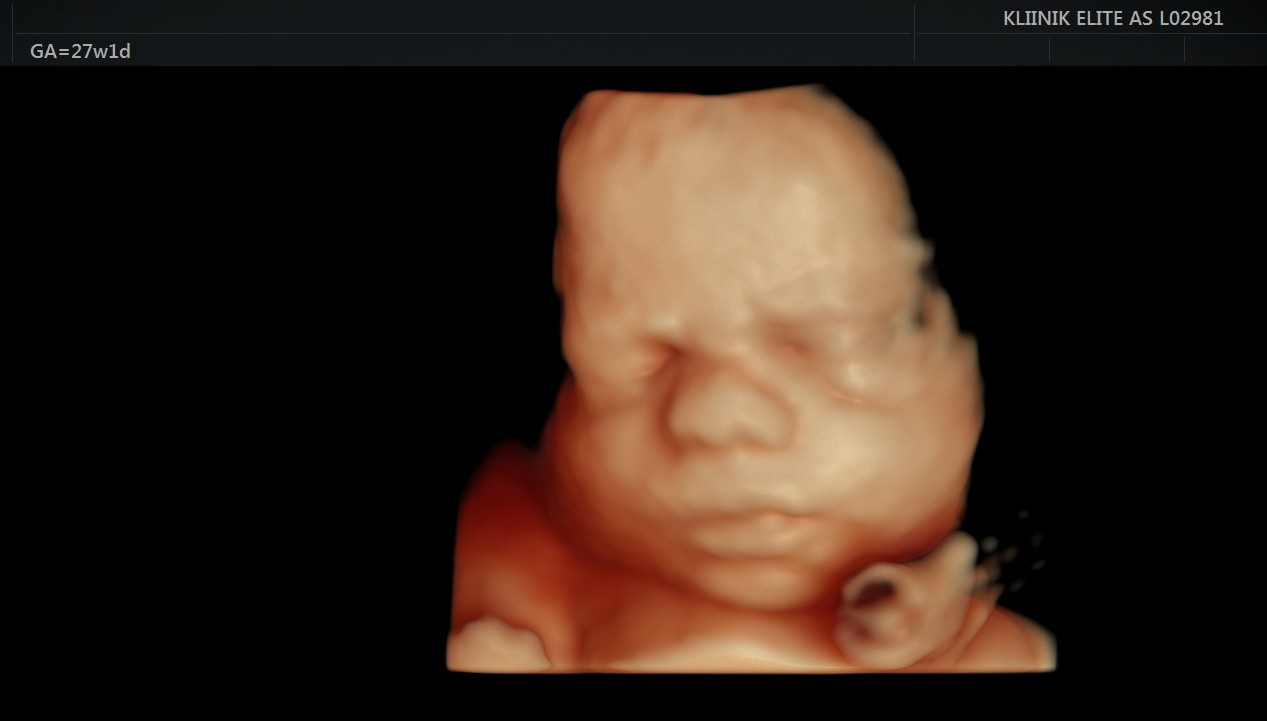

Kaelalülid on selgelt nähtavad. 23. nädalal kaalub loode umbes 550 grammi. 23. nädalast on hea visualiseerida 4D ultraheliuuringu käigus loote näojooni.

24. nädalal on loode umbes 30 sentimeetri pikkune ja kaalub umbes 650 grammi.

- Soovi korral 4D ultraheliuuring (24.–32. nädal)

Loote kaal on umbes 1 kilogramm ja ta on 35 sentimeetri pikkune. See on parim aeg 4D ultraheliuuringu käigus loote näo vaatamiseks.